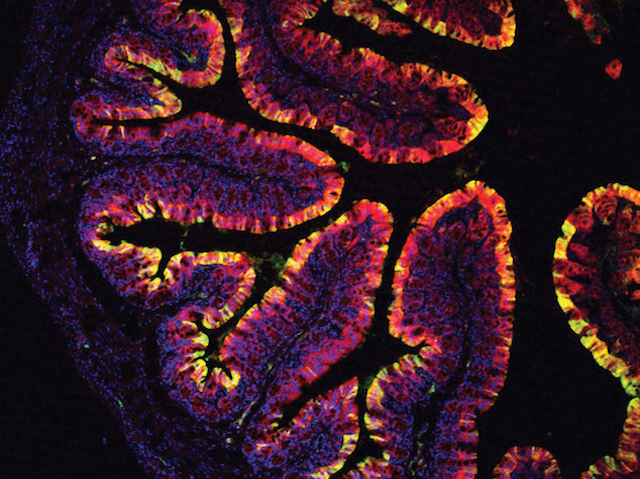

Cabbages for Colons

Chemical produced during the digestion of brassicas (kale, cabbage etc.) may be effective at preventing colon cancer

Most people understand the importance of eating their greens. But, in case you're someone that still balks at broccoli and sidesteps sprouts, research provides yet another incentive to add something green to your plate. According to experiments examining mouse colons (one pictured), a chemical produced during the digestion of kale, cabbage and other members of the Brassica genus – indole-3-carbinol– may be effective at both reducing colon inflammation and preventing colon cancer. When a strain of mouse normally prone to gut inflammation and cancer was given a diet rich in indole-3-carbinol, the animals’ colons were protected against inflammation and tumours. Furthermore, if such mice fed a normal diet began developing colon cancer, switching them to the indole-3-carbinol diet, reduced the number and malignancy of tumours that grew. Whether the results will hold true in humans is not known, but regardless it wouldn’t hurt to eat an extra sprout or two.